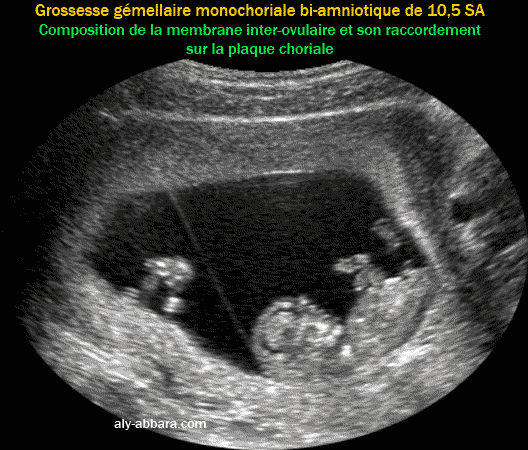

• Image échographique montrant le type de placentation d'une grossesse gémellaire mono-choriale bi-amniotique (vrai jumeaux).

• On peut remarquer que cette cloison (ou membrane inter-ovulaire) qui sépare les deux cavités ovulaires est composée seulement des deux amnios.

• Le raccordement de la membrane inter-ovulaire au niveau de la plaque choriale prend l'aspect de " T " ; ce raccordement est connu sous le nom du signe de T qui témoigne de la monochorionicité.

• Cette forme de placentation (monochorale ; bi-amniotique) se voit dans 70 % des grossesses gémellaires monozygotes (vrais jumeaux).